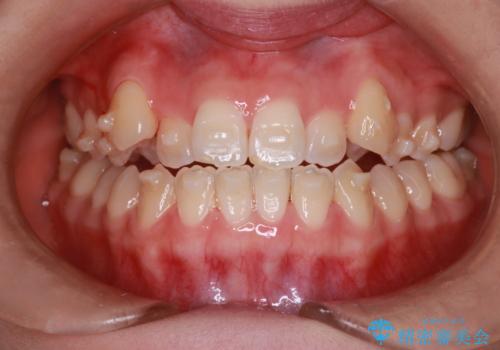

MARPEで非抜歯矯正|オープンバイトと八重歯を改善

- 治療計画

上顎にTAD(矯正用アンカースクリュー)を設置し、MARPEにより骨格レベルで上顎の幅を拡大。数週間の拡大期間を経て十分なスペースを確保したのち、マウスピース型矯正装置(インビザライン)で歯列全体を整えました。八重歯もアーチ内に自然に収まり、非抜歯で審美性と機能性を両立。治療後は「噛み合わせが安定して笑顔に自信が持てるようになった」とご本人にも大変満足していただきました。